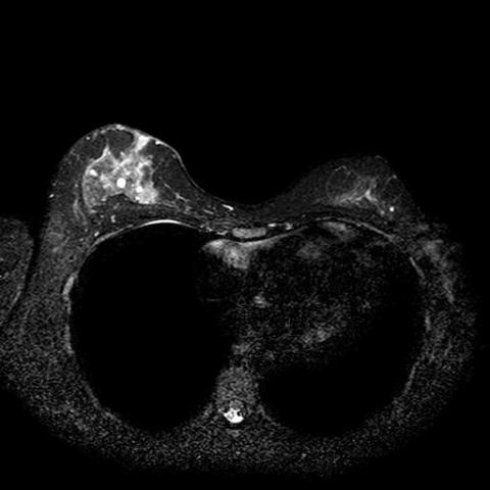

RISONANZA MAGNETICA (ALTO CAMPO) 1,5T

• Rm Femore anche Con Mdc

• Rm Ginocchio anche Con Mdc